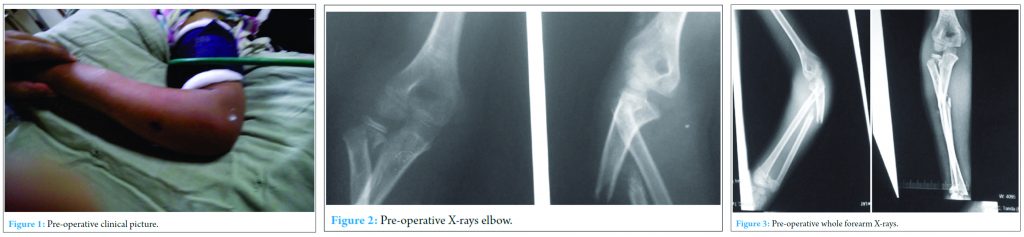

An 11-year-old, right-hand dominant boy presented in casualty with history of fall from window on his left hand1 day back with pain, swelling and deformity in the left forearm with bleeding from left forearm which was dressed at local hospital and loss of movement of thumb and fingers of left hand. On examination, there was a wound of size 1 cm on mid-forearm over the ulnar aspect (Fig.1). Extension of fingers at metacarpophalangeal joints and thumb was lost with intact sensations suggestive of posterior interosseus nerve involvement. Wrist movements could not be assessed due to pain in the wrist. No vascular was deficit was present. X-rays were performed which suggested type two epiphyseal separation of the proximal radius with fracture shaft of the ulna with lateral angulation (Fig.2). Radiocapitellar joint congruity was maintained in the views performed. X-rays of wrist suggested fracture both bones distal forearm, with Salter-Harris Type 2epiphyseal injury in distal radius and fracture of distal shaft of ulna (Fig.3). Intravenous antibiotics were started, and splintage was given, and the patient kept for surgery the following morning.